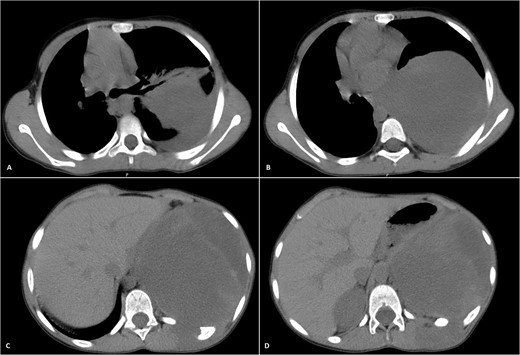

His postoperative course was uneventful. A chest CT was performed following the surgery, and the results revealed that the previous left lung mass had been completely removed without definite residue (Fig. 4). The patient is on close follow-up monthly with a physical exam, chest X-ray, and chest CT every 3–6 months. For the past two years, there have been no discernible clinical or radiological indicators of recurrence (Fig. 5).

Selected axial cuts of the patient’s chest–lung window. The previously mentioned left posterior chest wall mass is no longer seen with post-operative changes noted.